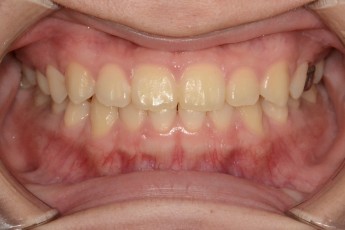

BEFORE & AFTER